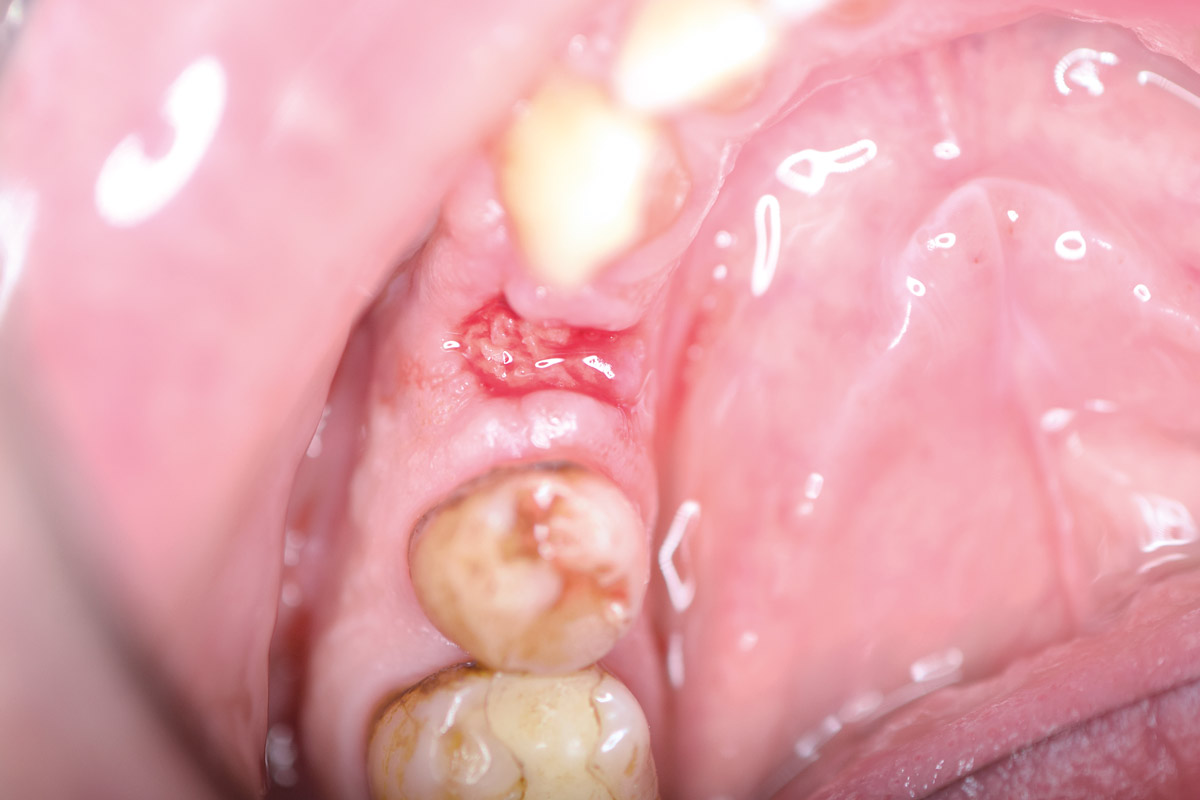

Initial clinical situation: 9 mm pocket depth associated with root fracture